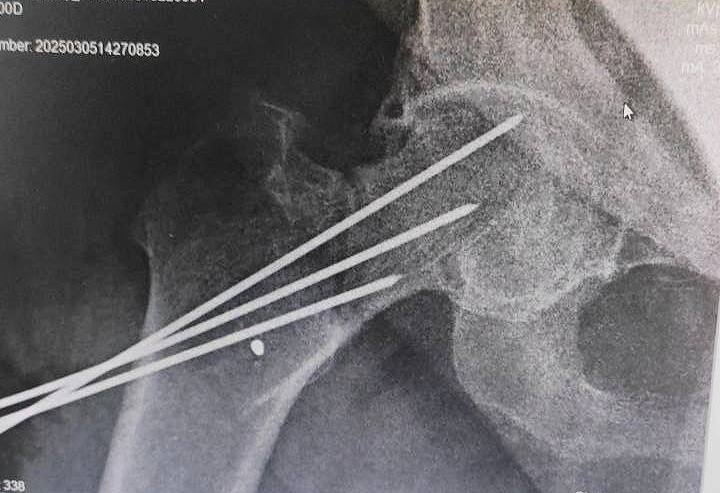

Son suyagi sinishi

Metal plastinka va vintlar yordamida son suyagini mustahkamlash

Vintli fiksatsiya

Son bo'yni sinishlarini kanyullyar vintlar yordamida davolash